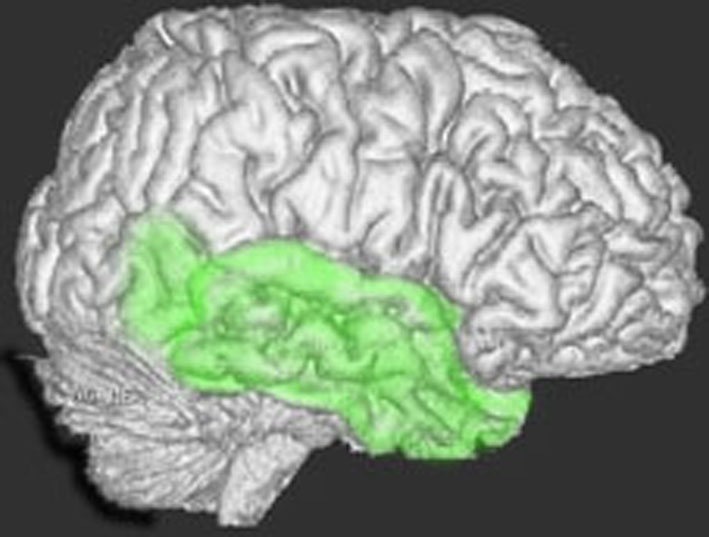

脳の底面(左)と正面(右)から

脳の右と左側面から

側頭葉の解剖図

側頭葉の解剖図です

側頭葉の解剖図です。表面からは見えませんが,深部の海馬というところには記憶の中枢があります。左側頭葉には言語の中枢もあります。聴覚や味覚,情動などの中枢も側頭葉にあります。